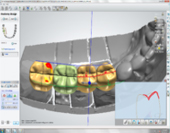

Without any incisions, Dr. Andrews removed the broken root and placed an implant along with a bone graft during the same surgery. Immediately, a temporary crown was attached to two other front upper teeth to form the ideal shape for the soft tissue profile. A few months later, 3D Intraoral scan was taken and Dr. Andrews used Virtual Prosthodontics (CAD) and Reverse Restorative Rehabilitation Protocol to design Full Contour Zirconia (FCZ) screw-retained Implant Crown.

Then the crown was milled (CAM) and sintered by a specialized Milling Center. Once it had been received, the FCZ restoration had been custom shaded and glazed at DENTOLOGY in-house lab. During the patient’s next and final visit, all-ceramic crown was delivered via screw-retained fashion to prevent any complications associated with cement retention under the gum margin (the most common reason for implant failures in intraorally cemented cases).